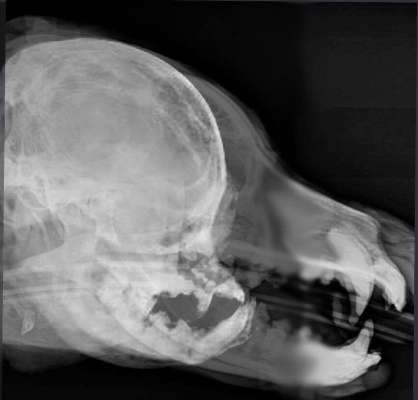

Mal wieder ein Bild zum direkten Vergleich

Hier noch der Beitrag aus dem das Bild stammt

Nur als Ergänzung, falls jemand sich damit beschäftigen möchte. Den Kommentar gab's zu Kommentaren eines "Röchelvideos" der TA Praxis Neulussheim, sobald der Tubus entfernt wird.